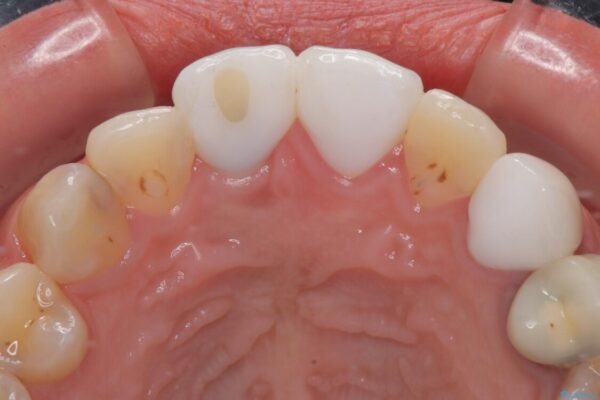

治療前

• 「抜歯してブリッジ」と言われた20代女性が選んだ治療とは|たった4か月で自然な笑顔に抜歯即時インプラント+審美補綴の症例 治療前画像

精密検査の結果、右上中切歯には**フェルール(歯の周囲の健全な歯質)**がほぼ存在せず、このままの状態での保存は困難と判断しました。

▶左上中切歯

土台を再度丁寧に整え、オールセラミッククラウンにて補綴

▶左上犬歯

根管治療行い感染除去した後、最終補綴はオールセラミッククラウンにて審美的に